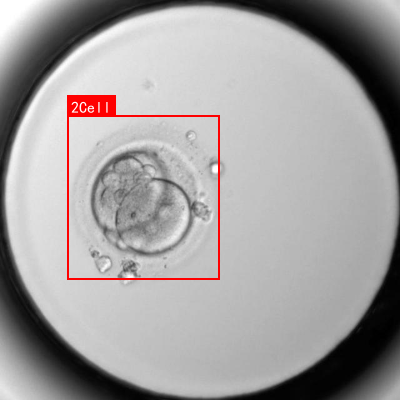

如上图所示,这是一张典型的二细胞期胚胎显微图像,两个大小相近的圆形细胞紧密相连,呈上下排列结构,整体形态类似数字"8"。这种形态特征是胚胎发育早期的关键识别点,不同发育阶段的胚胎在细胞数量、排列方式和形态特征上存在显著差异。

上图展示了一个典型的双细胞期胚胎形态特征,两个大小相近的圆形细胞紧密相连,细胞边界清晰。这种形态特征是Faster R-CNN模型需要学习的关键特征之一。模型通过多层卷积和池化操作,逐渐提取胚胎图像的深层特征,然后通过RPN生成候选区域,最后通过RoI Pooling层对每个候选区域进行特征提取和分类。

上图展示了一个胚胎显微图像样本,红色方框标注了待分析的胚胎区域。胚胎呈圆形结构,内部可见多个细胞团块,细胞间界限清晰。这种图像需要经过预处理后才能输入模型进行训练和推理。